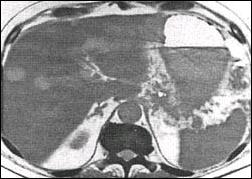

Pseudocysts disappeared completely in 42 of 47 endoscopic drained patients (89%) (Fig.5). In the remaining 5 cases drainage was not successful. 6 (14 %) of these 42 patients suffered a relapse until 38 months after removal of the drainage. The patients whom went communication were 22 patients and no other palindromia was not observed within a follow-up of 5 to 11 years . In 7 patients (15%) early complications such as occlusion or dislocation of the prosthesis or bleeding into the cyst occured. In 6 of these cases the prostheses were replaced because of malfunction. 6 patients had to undergo surgery, 3 patients because of relapsing cyst, 2 patients due to insufficient drainage of the cyst and one patient with a bleeding which could not be treated endoscopically .

Fig. 5. The pancreatic pseudocyst disappeared completely

after the transgastrale drainage in 5 week